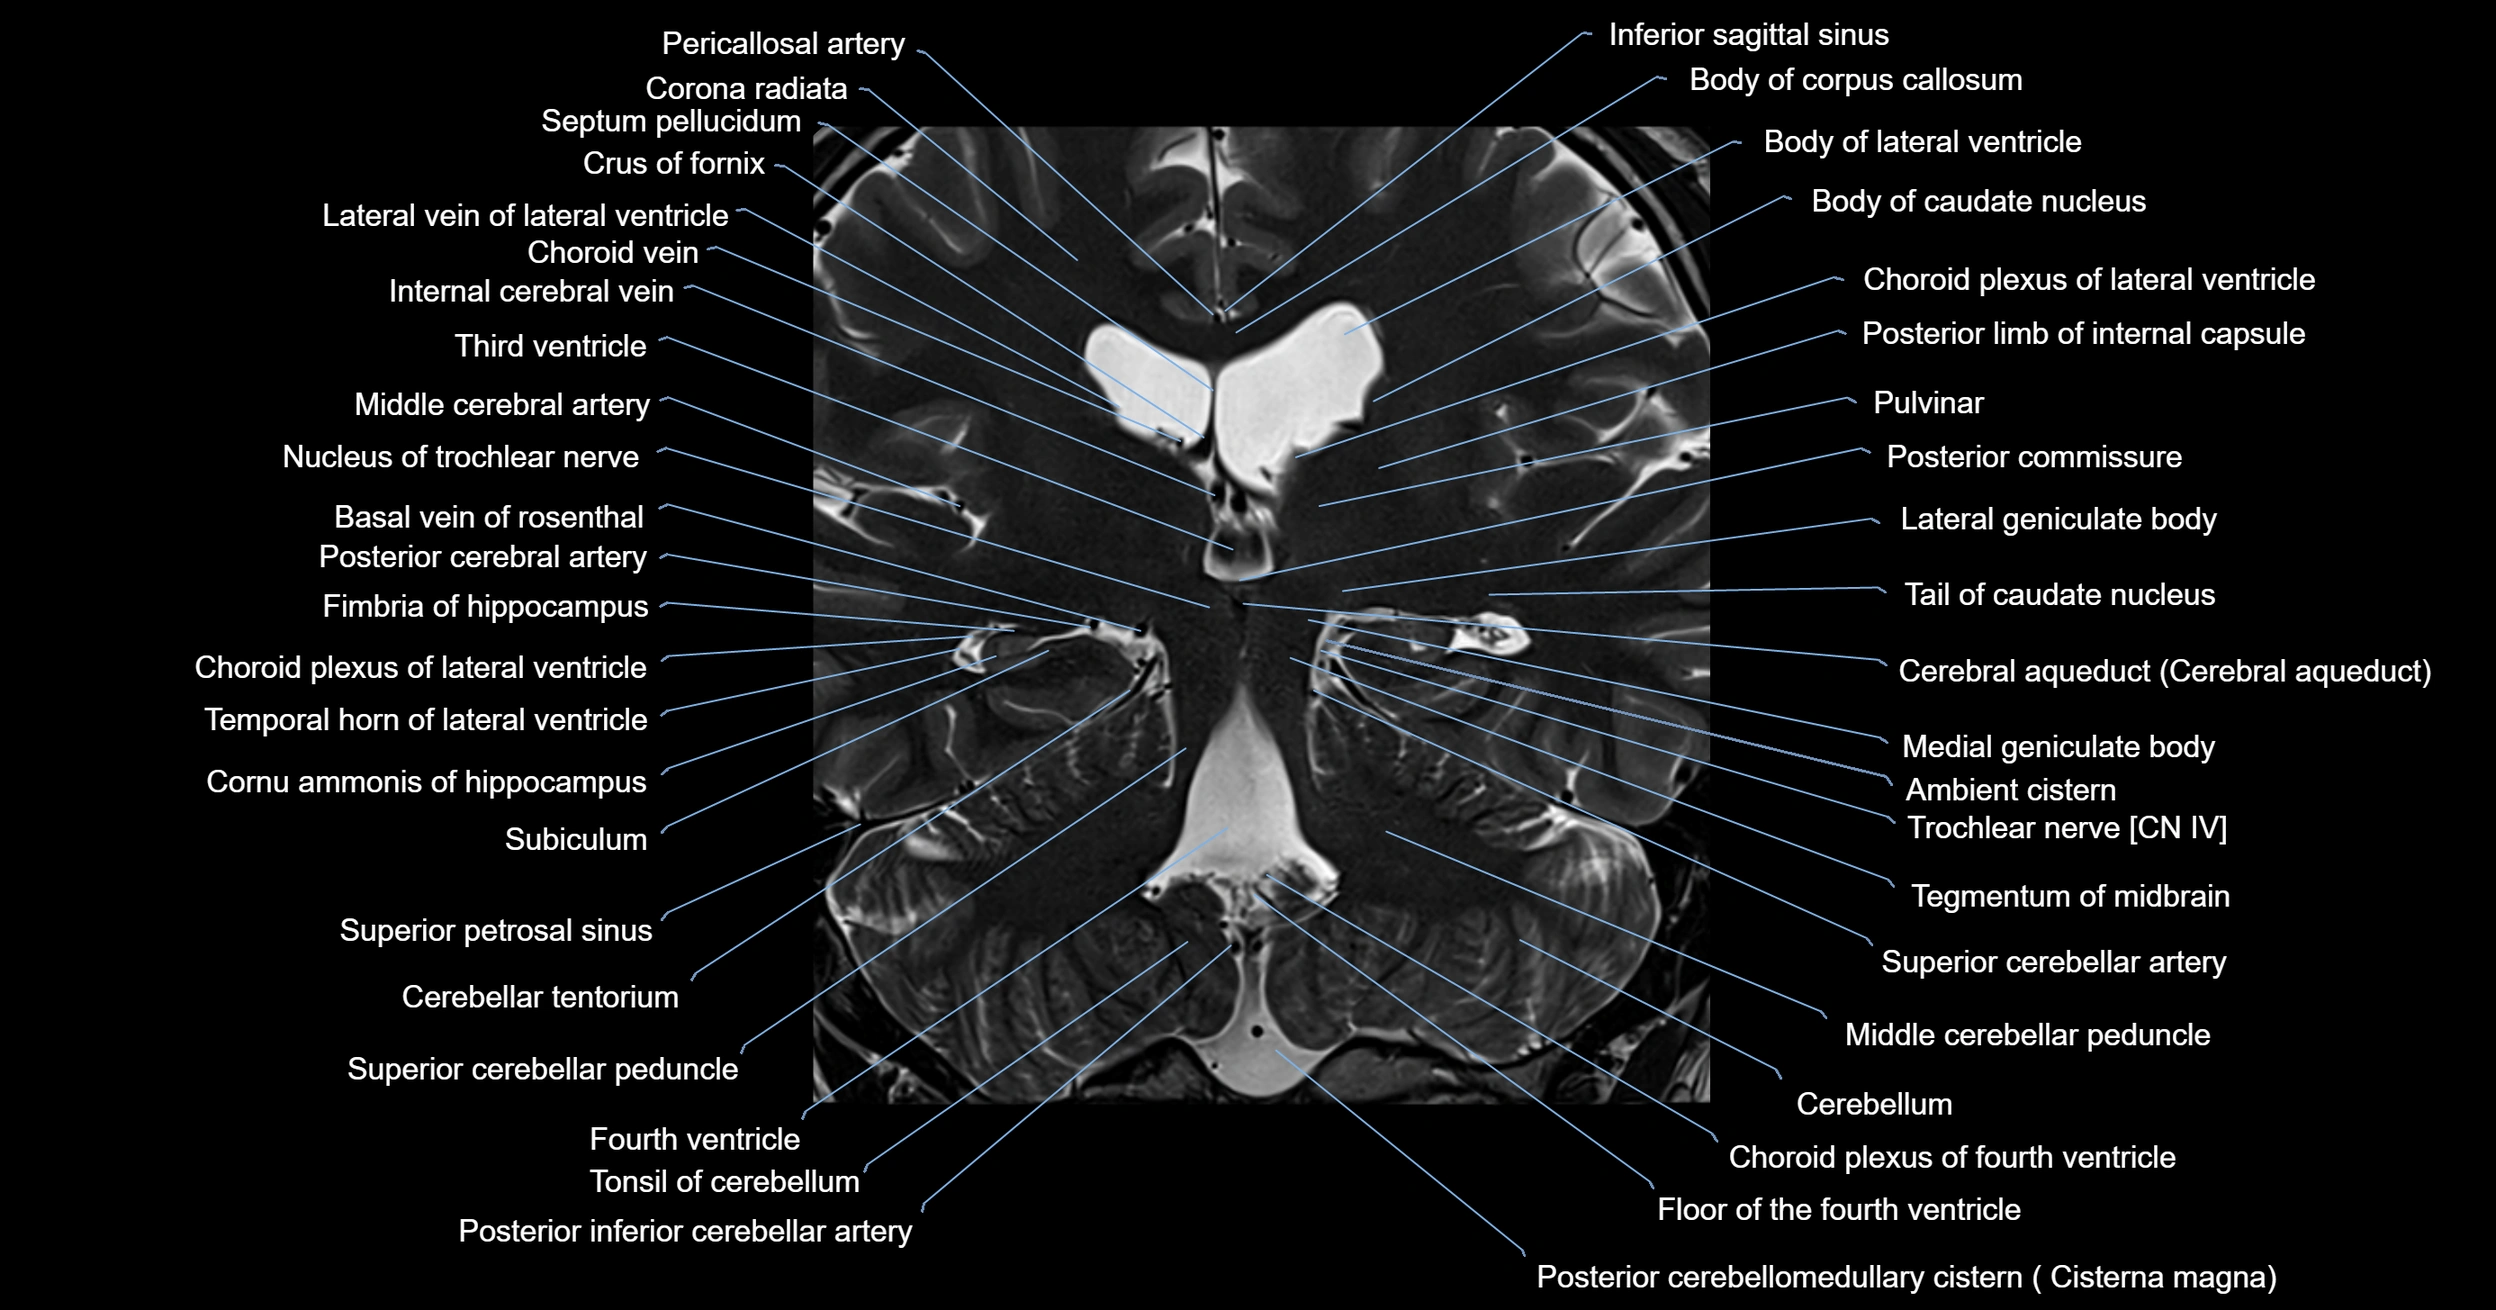

MRI images